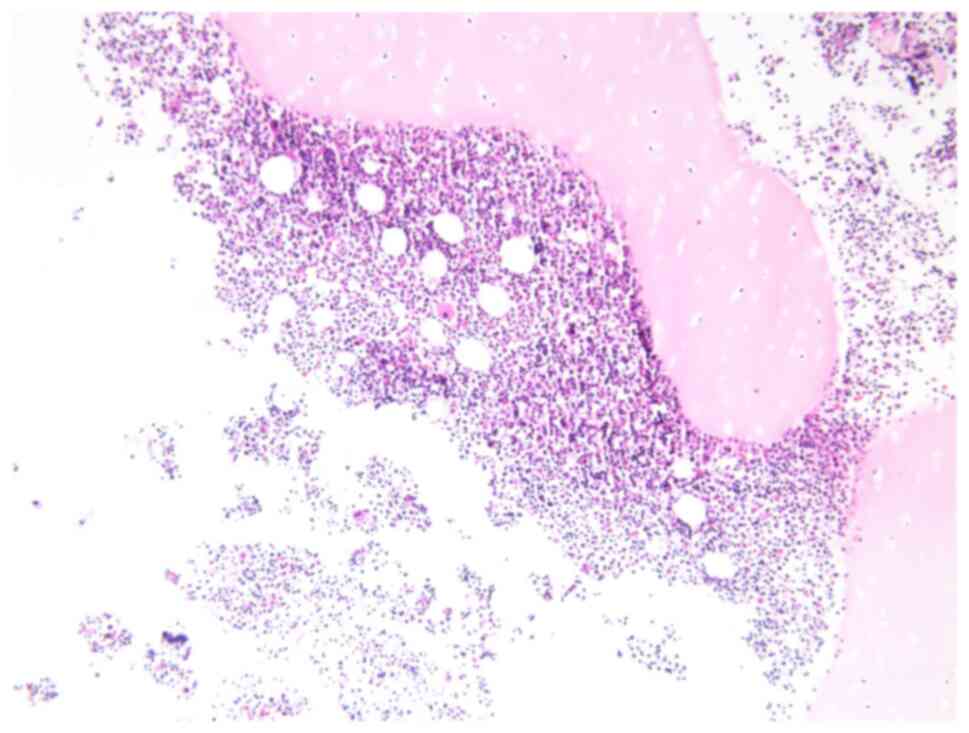

Laboratory examinations revealed severe microcytic hypochromic anemia, with hemoglobin value of 80 g/l. T-SPOT showed no abnormality. Blood and pleural effusion cultures were negative. The pleural fluid test suggested chylothorax. Contrast-enhanced chest CT (Figs. 1 and 2) showed multiple lymph nodes in bilateral cervical roots and mediastinum, which were fused into clusters, and the trachea and mediastinal great vessels were surrounded. Furthermore, there was multiple thickening of interlobular septa in the right lung, multiple inflammations in both lungs and atelectasis in the left lung, and massive pleural effusion on the left side. Positron emission tomography (PET)-CT showed soft tissue thickening around the trachea, blood vessels, and thyroid gland in the lower neck and the mediastinum, especially in the anterior and superior mediastinum. The pulmonary interlobular septum was significantly thickened, and the bronchial vascular bundle was thickened, accompanied by multiple patchy shadows of increased density and consolidation. The pleural effusion of the child was chylous (Fig. 3). Biopsy of the mediastinal mass revealed patchy, small lymphocytes with few thymus corpuscles. The tumor tissue was fissured and had a sparse reticular structure (Fig. 4). Immunohistochemistry results revealed the following: D2-40 (+), CD31 (+), Ki67 (1%+), SALL4 (-), SOX-10 (-), SMA (-), TDT (-), CD5 (-), CD117 (-), PLAP (-), AFP (-), HMB45 (-) and tissue changes consistent with the vascular origin of the tumor, inclined to lymphangioma.

Figure 4

Biopsy of mediastinal mass revealed patchy small lymphocytes with a few thymus corpuscles, which were fissured and had a sparse reticular structure.